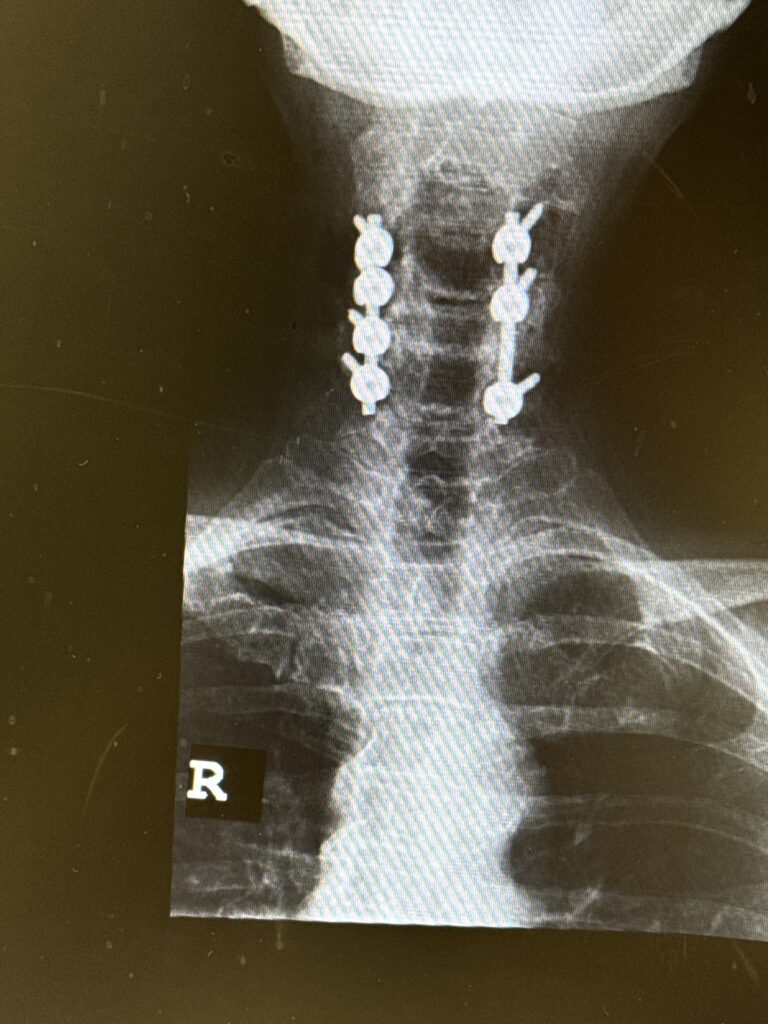

Patients may require an occipital-cervical fusion for both cranio-cervical and atlanto-axial instability, depending on the anatomy. Patients who have long segment posterior cervical fusions can sometimes […]